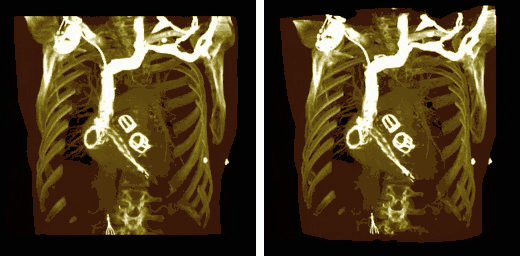

Volume rendering can be applied to the voxel data in the successive rotation manner described for MIPs above, as illustrated by the results in the following figure:

Note that the volume rendering can be contrast enhanced so as to threshold, for instance, through the voxel values to eliminate low attenuating surfaces, as illustrated in the following figure:

Note also that the colour look-up table (CLUT) can be varied to highlight features of particular interest, as shown in the set of images below:

The influence of the opacity table is illustrated in the following example images: